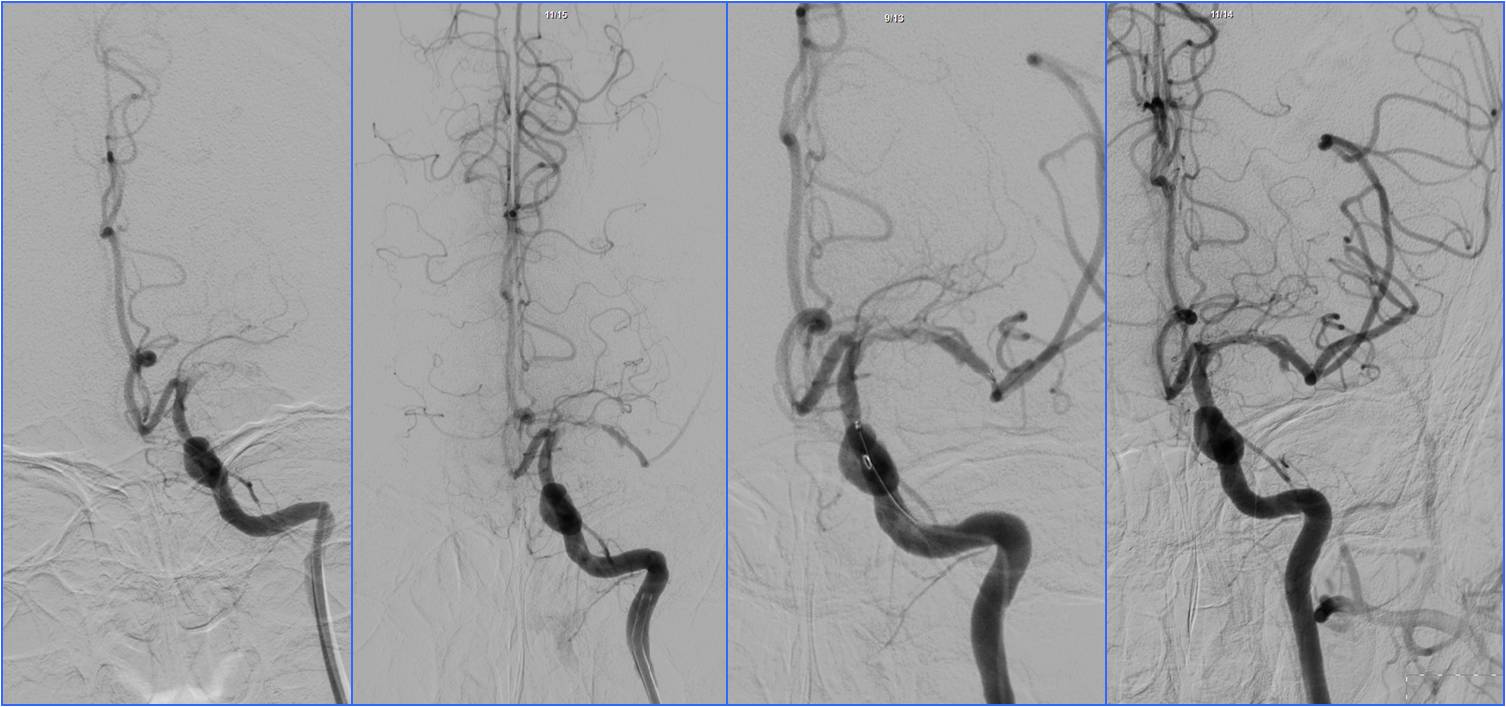

》11:56头MRA。

▼11:11复查头CT

▼11:56头MRA

》准备介入血管内治疗,患者症状自行缓解。后又加重,症状波动2次。

》13:22进入导管室行血管内治疗。行气管插管全身麻醉。

》DSA见基底动脉闭塞,Solitaire支架取栓后见基底动脉重度狭窄,Gateway球囊扩张,置入Wingspan支架。

》术后24h完全恢复,NIHSS评分0分。

▼13:49DSA

▼支架取栓后基底动脉残余重度狭窄

▼基底动脉支架置入术

▼4天后复查MRA